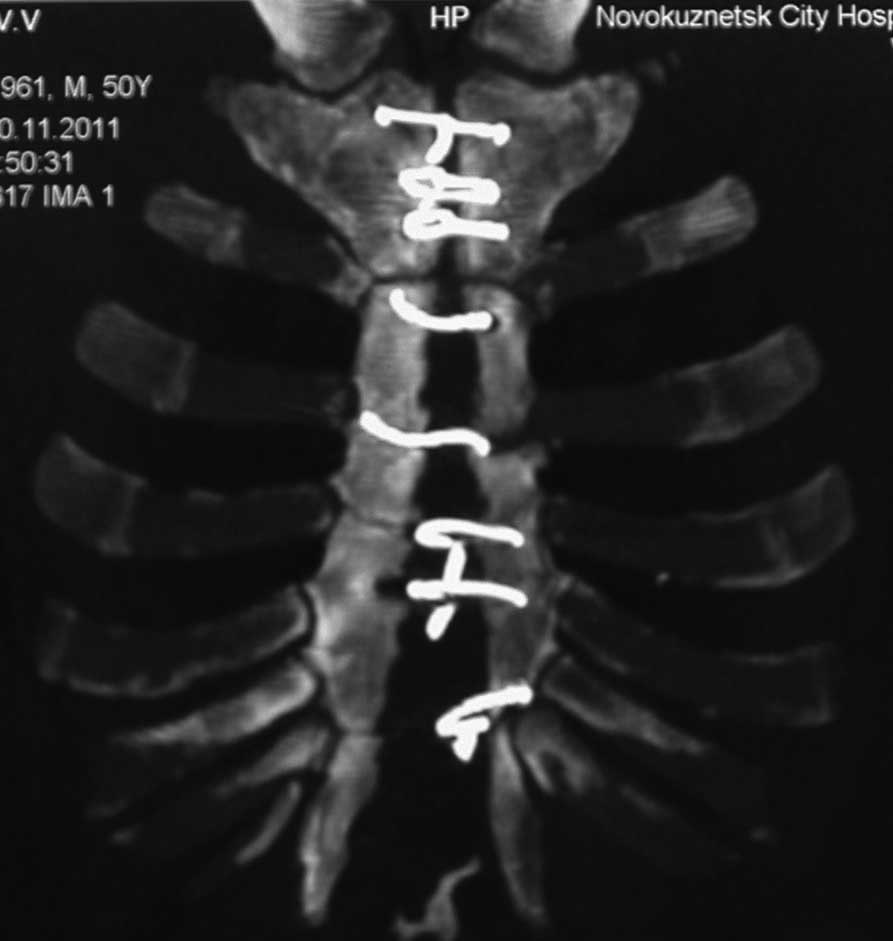

[Ortho] несращение грудины

Sorry основной снимок